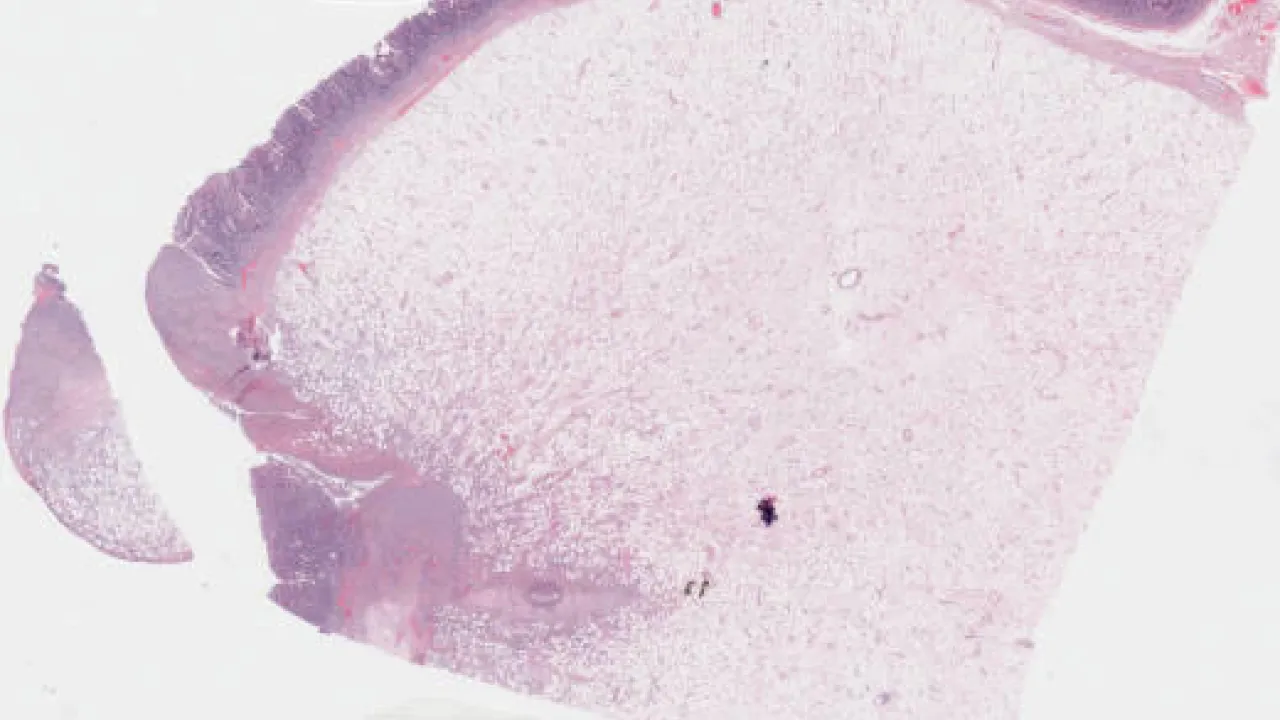

Skin, basal cell carcinoma